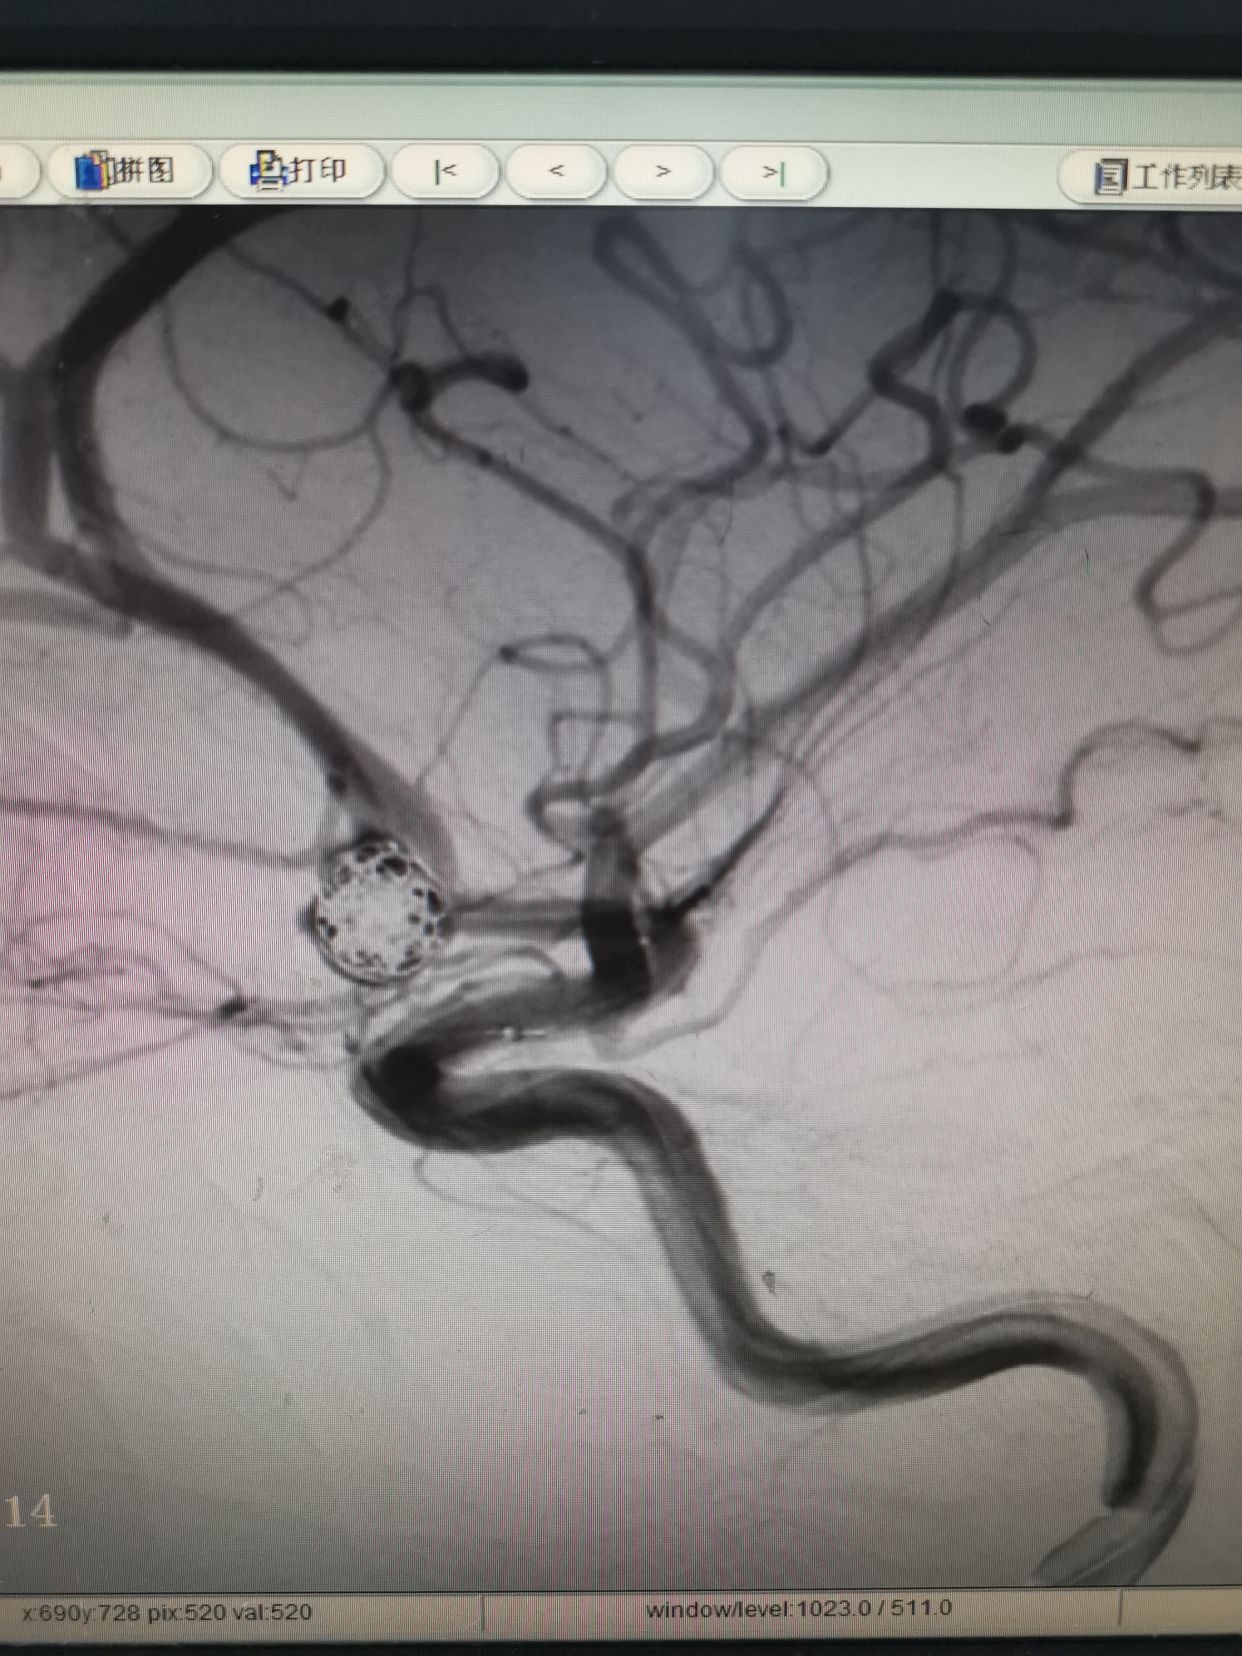

术后动脉瘤不显影,双侧大脑前显影。右侧略差。

介入填塞过程顺利,用时大约半小时,期间予20%甘露醇250ml静滴。后立即转入手术室行右侧开颅脑内血肿清除术。